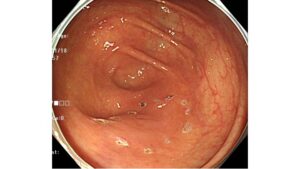

特殊光(NBI)による色差でみつける早期胃癌シリーズ②